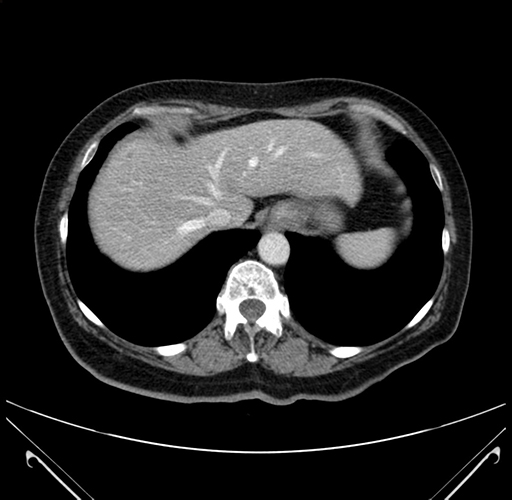

Pre-Chemo: Coronal Venous

Coronal Venous